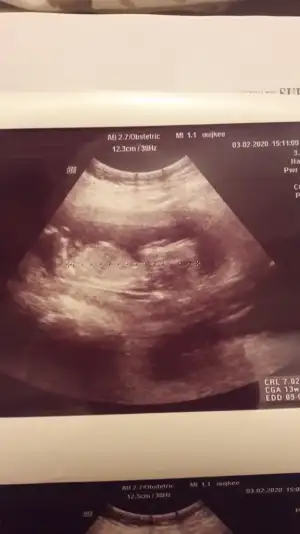

20200203_163234.webp

Gecen 12 haftalik istemistiniz bugun cekildik yine :) tahminde bulunabilir misiniz